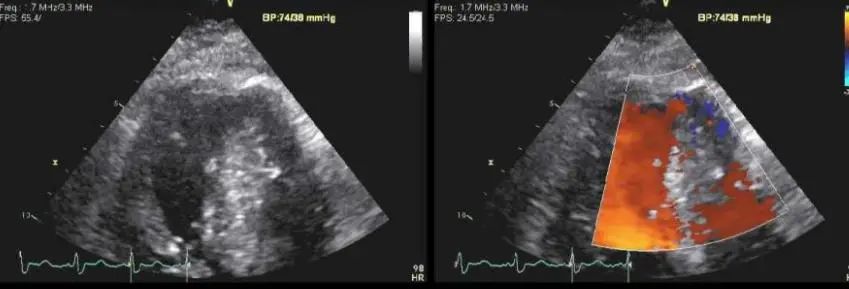

此培训为MAYO诊所推出的心内科fellow系列培训之一,主要目的是能够使大家学习到AMI以后心脏机械并发症的识别和诊断,还有ACS的非心脏的并发症的表现,以及临床中存在与ACS临床上有相似之处的非心脏疾病。 急性心肌梗死后出现的并发症,分为心脏性和非心脏性的,心脏并发症又包括心电学方面的并发症以及机械并发症,非心脏性并发症包括血栓栓塞和出血,还可能出现与心包相关的并发症。 心脏机械并发症包括就是破裂性和非破裂性的2类,破裂性并发症包括游离壁破裂、室间隔穿孔和乳头肌断裂,其中游离壁破裂既可能是直接的穿孔,也可以是亚急性破裂形成假性动脉瘤这样包容性的破裂。而非破裂性机械并发症包括严重的左室心力衰竭,右室梗塞,左室壁动脉瘤以及缺血性二尖瓣反流。 从根本上来说,这些严重并发症的发生都与心脏的泵功能衰竭有关,泵功能的衰竭造成了血流动力学不稳定以及基线的电不稳定性。 第一节:非破裂性机械并发症 非破裂性机械并发症,即严重的左室心力衰竭——心源性休克,右室梗塞,左室壁动脉瘤以及缺血性二尖瓣反流。 1、 心源性休克:在心梗发生时,发生心源性休克的主要原因就是大面积的心肌梗死,那么如果要导致心脏泵功能衰竭,左室心肌质量至少要损失40%以上。其他导致心源性休克的原因还有右室梗塞、心脏破裂以及快速和缓慢性心律失常。 2、 右室梗塞:也是导致心源性休克发生的重要原因。在下壁心梗的患者中,大概有33%的患者同时也发生右室梗死,这种情况多见于RCA近端闭塞,与高死亡风险相关。在所有下壁STEMI者中都要考虑是否同时存在RV梗塞,心电图V1和RV4导联ST段抬高超过1mm为其特异性心电图改变(图1)。 图1. 右室梗塞的心电图表现 3、 右室梗塞为什么会导致患者发生心源性休克呢?从病理生理上讲,右室急性缺血时会致其收缩不良,导致RV每搏输出量和峰压降低,继而是左室前负荷降低,心输出量降低;另一方面,急性缺血还同时使右室舒张功能受损,此时右心充盈压显著增加,并且由于右室急剧扩张,会在心包内占据很大体积,使得心包内压力显著增加,这些综合造成的结果使RV和LV的充盈减少。左心充盈压下降而右心压力不断升高,最终导致低血压、肺血流减少、颈静脉压升高,其临床结果可能类似于心包填塞以及缩窄性心包炎。 4、 左室壁动脉瘤(图2):首先提出一个问题供大家思考,以下有关左室壁动脉瘤的说法哪一个是正确的?1左室壁动脉瘤只局限于心内膜下;2有一个相对狭窄的颈部;3是否都与前壁心梗有关;以及4容易有血栓的附着,并且心包是组成瘤壁的一部分。实际上,左室壁动脉瘤在STEMI后的发生率<5%,前壁梗死的患者更易发生,及时进行再灌注治疗可以降低其发生率。它突出于心腔外侧,瘤壁就是左室壁,颈部和底部的比例大约是1:1,可以出现附壁血栓。所以上述说法中只有3是正确的。 图2. 左室壁动脉瘤示意图,O;颈部,D:底部,LA:左心房,LV:左心室,AO:主动脉 5、 缺血性二尖瓣反流:为心梗后左室重构所致,表现为乳头肌移位、乳头肌功能不良使瓣叶活动受限以及瓣环扩张(图3)。治疗的焦点集中于及时的再灌注治疗、利尿剂的应用和后负荷的降低,如果遗留严重的二尖瓣反流,则会导致心梗后的远期生存率下降。 图3. 瓣环扩张(A)、乳头肌功能不良致瓣叶活动受限(B)导致大量MR 第二节:破裂性机械并发症 破裂性并发症包括游离壁破裂、室间隔穿孔和乳头肌断裂,其中游离壁破裂既可能是直接的穿孔,也可以是亚急性破裂形成假性动脉瘤这样的包容性破裂。大多数破裂性并发症都发生在AMI的第一个24小时之内,剩余的则发生在1周之内。通过超声心动图可以发现MI的机械并发症,包括急性乳头肌断裂、下段室间隔断裂、上段室间隔断裂以及二尖瓣脱垂。 1、 乳头肌断裂所致二尖瓣反流(图4):乳头肌断裂常发生在MI后的2~7天,急性缺血事件发生时,从心外到心内的压力梯度增加,心内灌注降低,乳头肌属于心内结构,缺血的敏感性增加。一旦出现需要外科手术治疗。 图4. 乳头肌断裂(箭头所示) 2、 室间隔缺损(图5):属于MI后的罕见并发症,多于梗死后3~5天发生,在梗死后即刻或者第一个24小时内就可以发生,部分与患者进行的纤溶治疗有关。由于再灌注治疗的开展,目前发生率已经由2%降至0.2%。破裂发生在健康心肌和坏死心肌的交界处,在前壁心梗时,缺损位于室间隔心尖部,下壁心梗时缺损则位于下-后间隔基底段,RV梗死及功能失常者预后不良。 图5. 前壁心梗(A)、下壁心梗(B)所致不同部位室间隔穿孔 3、 游离壁破裂:急剧的、常为致死性机械并发症;发生率<1%;MI后死亡约8~24%是由此而造成;通常在梗死后的5天内发生。好发因素包括1首次心梗,2前壁心梗,3老年患者以及4女性。 4、 亚急性破裂:是一种特殊类型的游离壁破裂,占所有游离壁破裂患者的约1/3,是因为附壁血栓和心包覆盖了穿孔部位所致,局部表现为假性动脉瘤(图6),临床上常比较隐匿,并且可能仅通过UCG发现,因此任何超声发现的心脏周围局部积液都需要引起怀疑并详细扫查。与真性动脉瘤(即左室壁动脉瘤)不同,假性动脉瘤的颈部狭窄,颈部与底部的比值<0.5,心包是瘤壁的组成部分。亚急性破裂的进展常是难以预测,可以进展至完全破裂乃至心包填塞,因此需要外科治疗。 图6. 左室假性动脉瘤示意图,O;颈部,D:底部,LA:左心房,LV:左心室,AO:主动脉 第三节:AMI的非心脏并发症 AMI的非心脏并发症主要包括血栓栓塞和出血,以及心包并发症。那么下面关于左室血栓的说法哪个是正确的呢?1下壁心梗更为常见,2如果不予治疗栓塞风险可达50%,3栓塞的风险取决于血栓的移动性和是否凸出于腔内。左室血栓常(图7)见于大面积前壁心梗,在再灌注前时代其发生率可高达40%,有再灌注治疗后这一几率已降至4~15%;经胸超声心动图是发现LV血栓的第一选择;心脏MRI的敏感性更高,但与超声心动图的特异性相似。由于心梗后不运动和运动障碍的室壁区域存在静止血流,因此如容易在局部形成附壁血栓。如果梗死部位为心尖部,且左室EF值减低达<30%,则存在血栓栓塞的高风险。如果未治疗,左室血栓发生栓塞的风险为10~15%,这一风险的高低还取决于栓子的移动性和是否突出于心腔内,早期且持续的抗凝治疗(3~4个月)可以降低栓塞风险。 图7. 左室心尖部附壁血栓 一图总结心脏机械并发症 第四节:类似ACS的非心脏疾病 通过一个有趣的病例,我们来学习一下在临床中可能存在类似于ACS表现的非心脏疾病。这是一个77岁老年女性,症状为头晕、恶心、呕吐,急诊CT除外了急性卒中,但心肌坏死标记物升高,心电图提示为Af、并且下壁前壁导联T波倒置,但超声心动图上仅表现为室间隔中下段至左室心尖部运动减低,没有看到下壁及前壁的运动异常。随后患者出现严重的高血压和心动过缓,并存在定向力、消化不良和眼球震颤,继续监测头CT及MRI,结果发现枕叶大面积脑梗。实际上,早在1947年,急性卒中所引起的ECG变化就已经被报道,病程中出现深大的倒置T波则被称为神经源性T波。在急性颅内事件发生时可以存在肌钙蛋白的升高以及心电图出现ST-T改变,在卒中的急性期,ECG诊断急性心梗的特异性会降低。 除急性脑血管病以外,以下疾病也会出现类似于ACS的临床发现,包括心电图异常和心肌坏死标记物升高,如特发性应激性心肌病,主动脉夹层,肺栓塞等等,需要及时进行诊断及鉴别诊断。 最后需要强调的是,超声心动图是发现AMI后心脏机械并发症的最重要检查,AMI发生后一周内必须行UCG检查以发现隐匿的高危并发症。